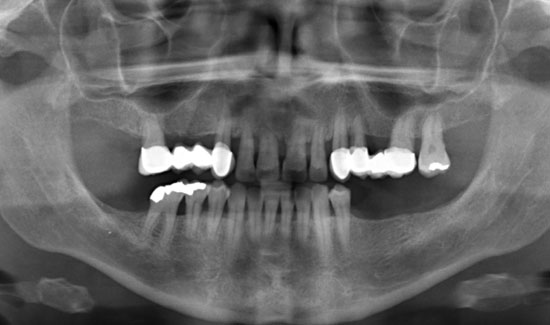

Abb. 3: Zustand nach Ozontherapie. Chlorhexidinverfärbung der Zähne